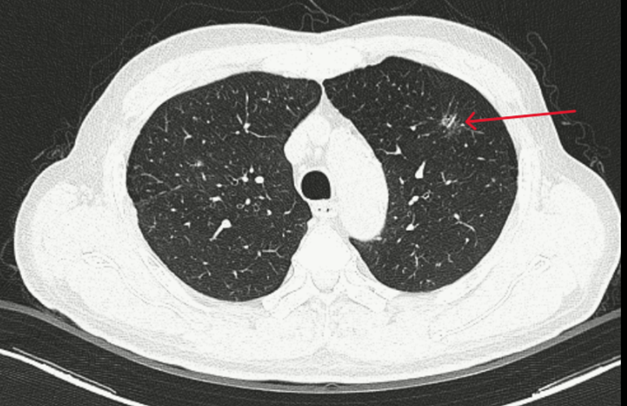

– Chụp CT ngực: Hình ảnh đám tổn thương kính mờ có bờ tua gai thùy trên phổi trái

Hình 1 : Thùy trên phổi trái có đám tổn thương kính mờ, bờ tua gai kích thước 10×13 mm.

Hình 4: Hình ảnh vài đám tổn thương dạng kính mờ bờ tua gai ở thùy trên phổi trái, lớn nhất kích thước 17×17 mm, tăng nhẹ hấp thu FDG (SUVmax: 2.4) – Theo dõi do viêm.

Xử trí: Tổn thương phổi trên CT được sử dụng AI để phân tích, xác suất nốt kính mở ờ thùy trên phổi trái là tổn thương ác tính khoảng 97%. Bệnh nhân được hội chẩn hội đồng có chỉ định phẫu thuật. Bệnh nhân được phẫu thuật nội soi cắt một thùy phổi kèm nạo vét hạch.